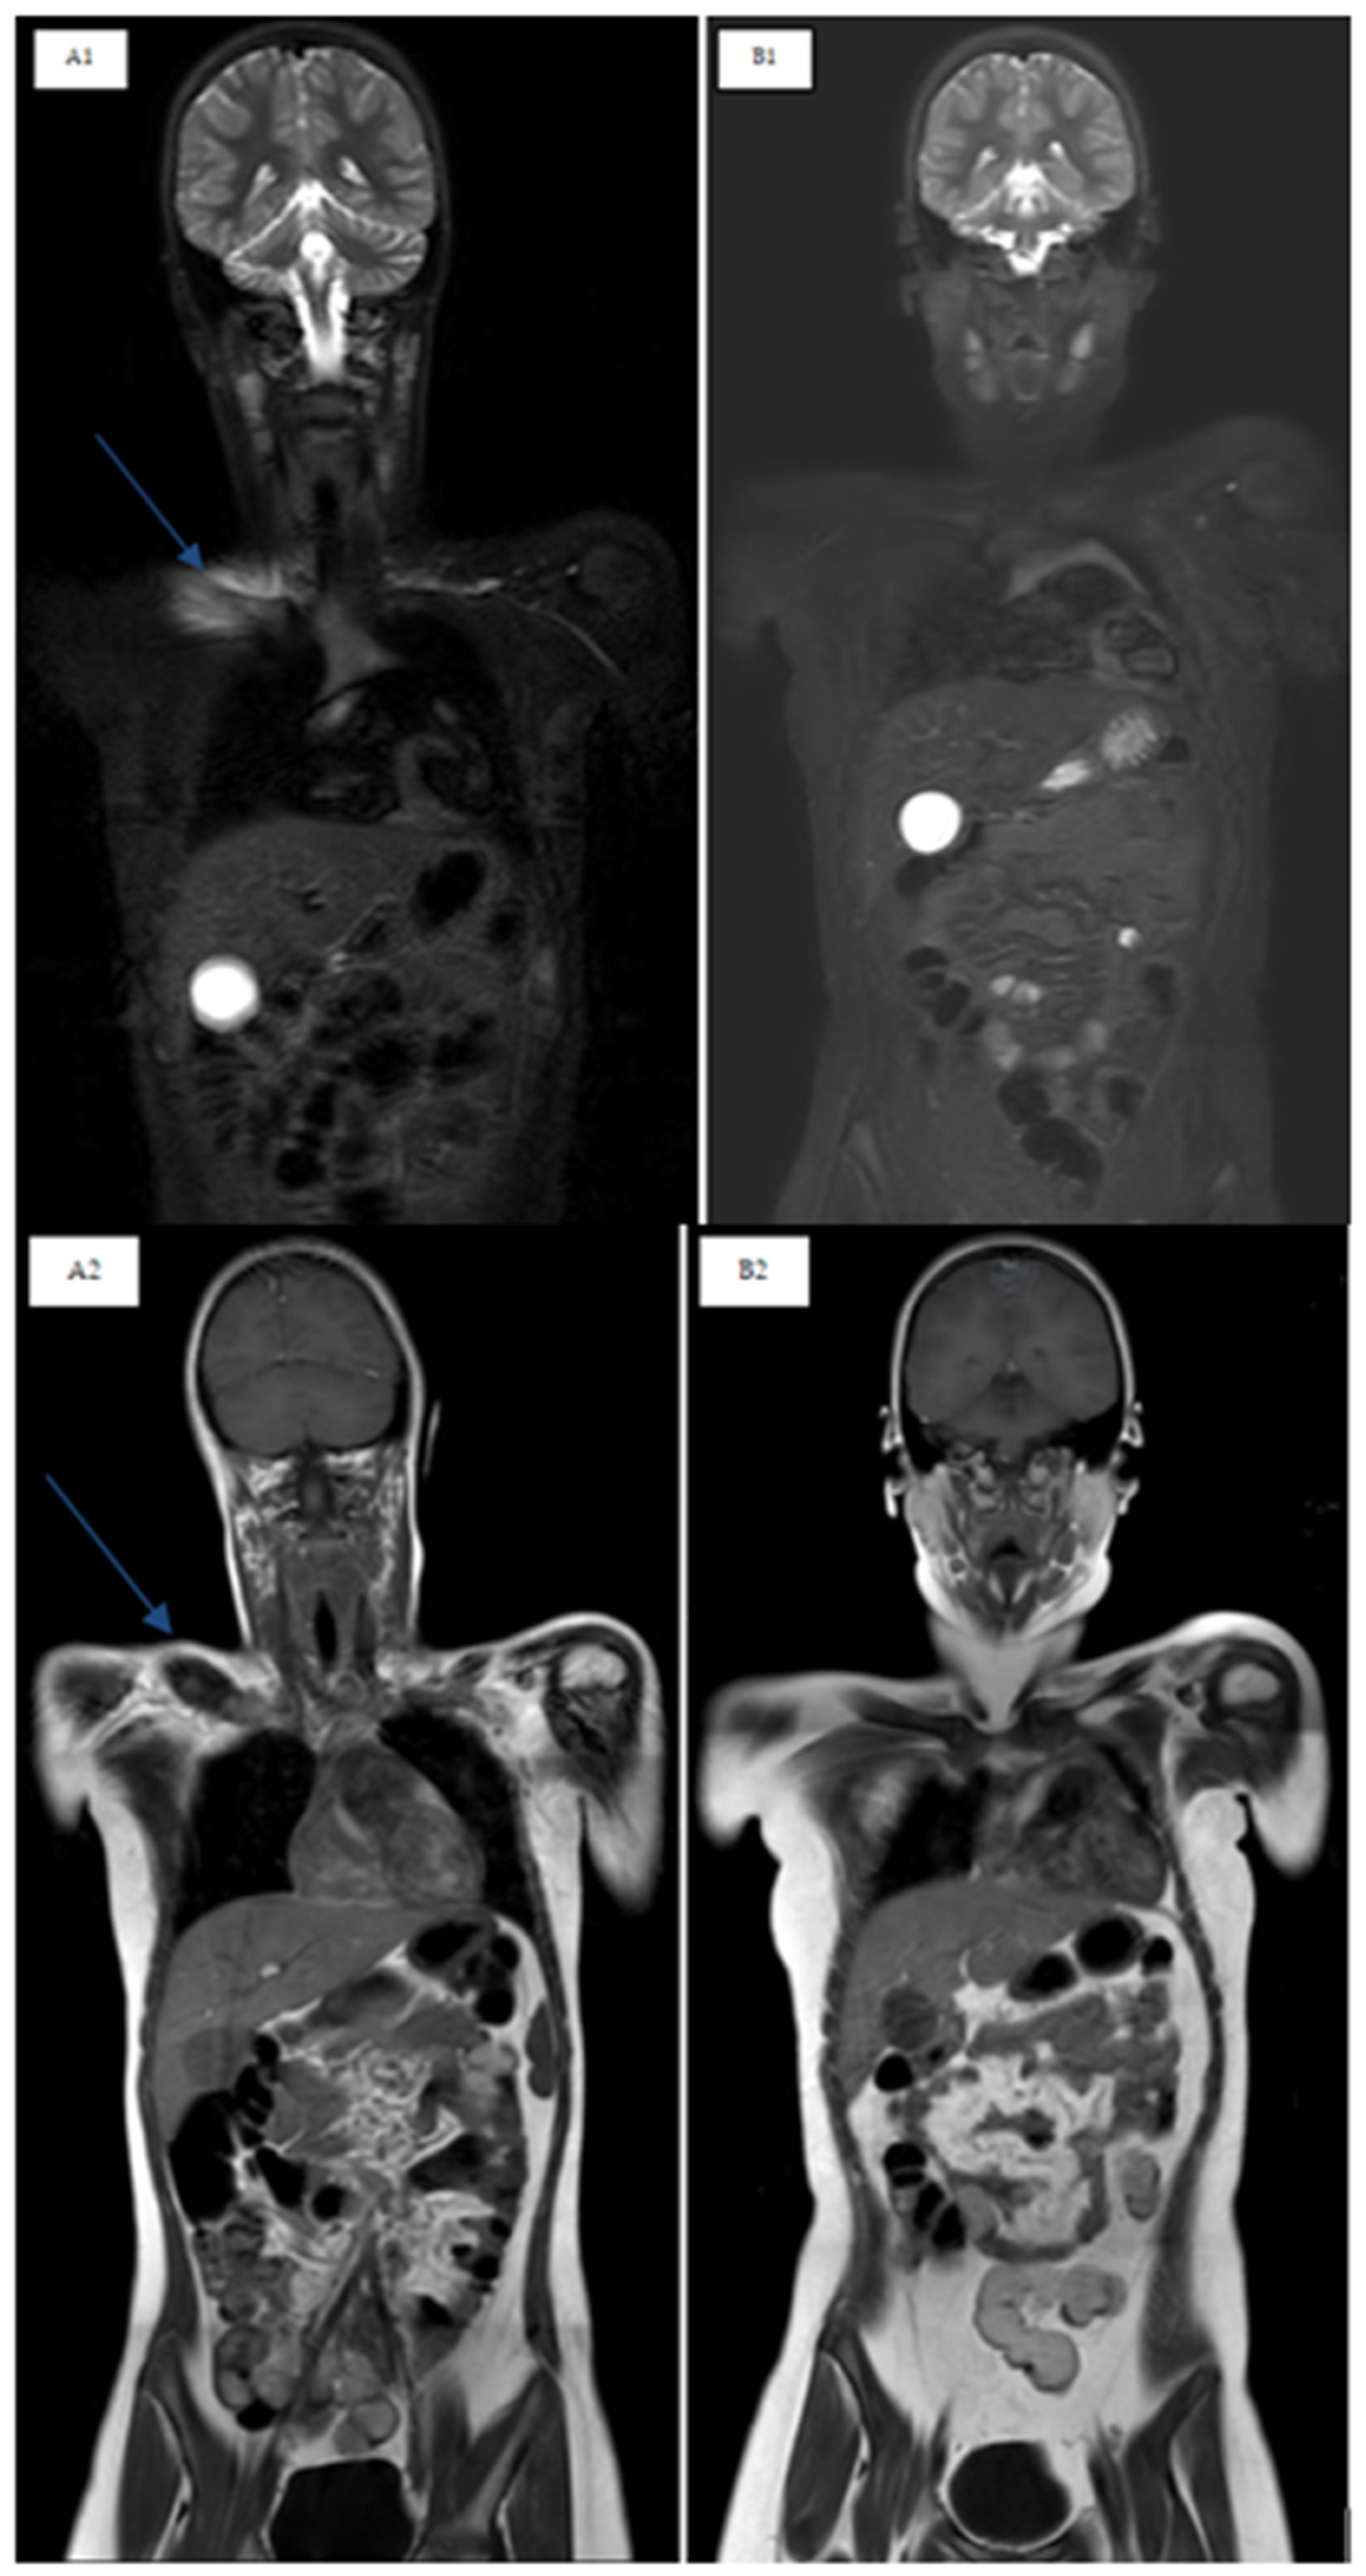

The aims of therapy are improving symptoms, preventing the progression of lesions and promoting bone health. The treatment of CNO, to date, has not yet been standardized. Nonsteroidal anti-inflammatory drugs (NSAIDs) represent the first line of treatment, proving their efficacy in a subgroup of patients [30,32]. However, the relapse rate remains high, and several studies show that 50% of patients treated with only NSAIDs relapse within 2 years [30,35]. Corticosteroids, bisphosphonates, methotrexate (MTX) and anti-TNFα (etanercept, adalimumab and infliximab) are used as second-line treatments with variable results [30,32]. Bisphosphonates and in particular pamidronate seem to have an important role in the management of this disease due to their rapid efficacy in bone remodeling by inhibiting osteoclastogenesis processes, reducing bone resorption and increasing bone mineralization [2,12,36,37,38]. Their efficacy in terms of the improvement of active lesions has also been reported [39]. In fact, in a time interval between 2 and 12 months it has been demonstrated that bone lesions were resolved in WB-MRI during follow-up among patients treated with pamidronate [33] (Figure 4).

Figure 4.

T2 STIR and T1 TSE sequences in the coronal plane. Right clavicle involvement in a CNO patient before and after pamidronate treatment. (A1,A2) Clavicle edema, at T0 pre-pamidronate in T2 STIR and T1 hypointensity; (B1,B2) regression of clavicle edema, at T12 post-pamidronate in T2 STIR and T1 hypointensity.